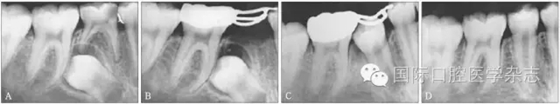

牙外傷引起的牙髓壞死、根尖周病變可能導致繼承恒牙發(fā)育或萌出方向的改變,因此,所有的乳牙外傷都應定期復查,嚴密觀察牙髓狀態(tài)及根尖周病變的發(fā)生。如果乳牙嚴重挫入,特別是乳牙冠向唇側移位,根向腭側移位時,X線片檢查發(fā)現乳牙牙根與恒牙胚大量重疊,應及時拔除乳牙。由于恒牙胚多在乳牙根的腭側,此時挫入的乳牙根可能會損傷壓迫恒牙胚,甚至牙胚移位,嚴重時即使拔除乳牙,也可能發(fā)生繼承恒牙釉質發(fā)育不全,甚至埋伏阻生、牙齒畸形。圖4顯示為一8歲男孩,因上中切牙未萌前來就診,追問病史為3歲左右乳牙外傷,但未行任何處理,后因外傷乳牙變色,牙齦流膿而在診所行拔除術,影像學檢查見右上中切牙為彎曲牙影像,牙冠與牙根不在同一軸線上[4]。

圖4 右上中切牙阻生(左),X線片顯示為彎曲牙(右)

Fig 4 Impaction of rightupper central incisor(left), X ray film showed the laceration tooth(right)